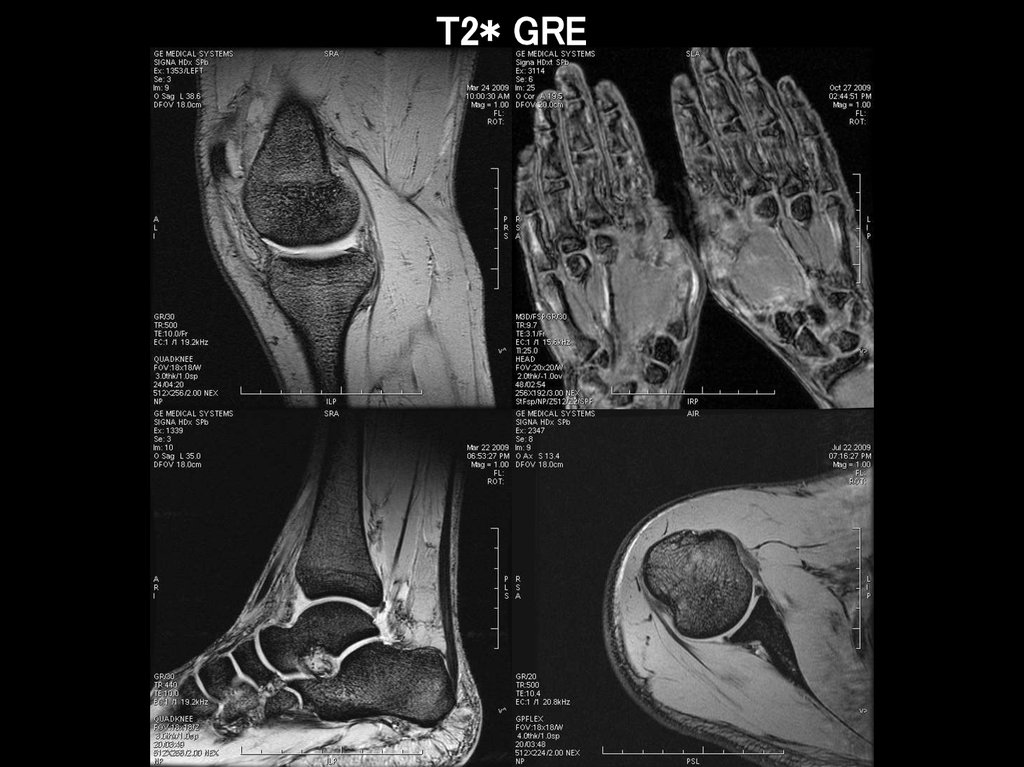

T2* GRE

36.